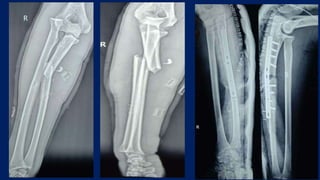

They did z shaped sagittal osteotomy, distracted, angulated and fixed

with one medio-lateral screw

Post op immobilised in AE slab for 6 weeks followed by gradual

mobilization

Rajasekaran S, Venkatadass K. "Sliding angulation osteotomy": preliminary report of a novel technique of treatment for chronic radial head

dislocation following missed Monteggia injuries. Int Orthop. 2014 Dec;38(12):2519-24. doi: 10.1007/s00264-014-2514-8. Epub 2014 Sep 11.

PMID: 25209346.